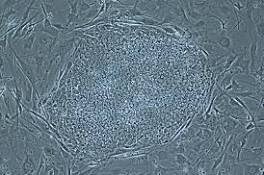

Kemudian, diteliti pada sukarelawan manusia, sampai saat ini sebanyak 100 orang telah bersedia untuk dijadikan obyek penelitian terapi stem cell ...

"Terapi stemcell tidak perlu lagi dilakukan ke luar negeri, tetapi juga sudah bisa dilakukan di Makassar," ujar dr Fonny Josh usai audiensi dengan ...

dr Fonny menjelaskan, saat ini terapi stemcell tidak perlu lagi dilakukan ke luar negeri, tetapi juga sudah bisa dilakukan di Makassar. "Dengan ...